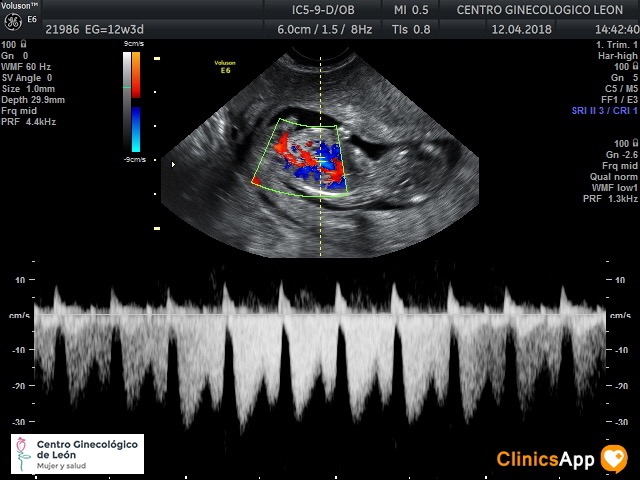

Ecografías del 12 de abril de 2018